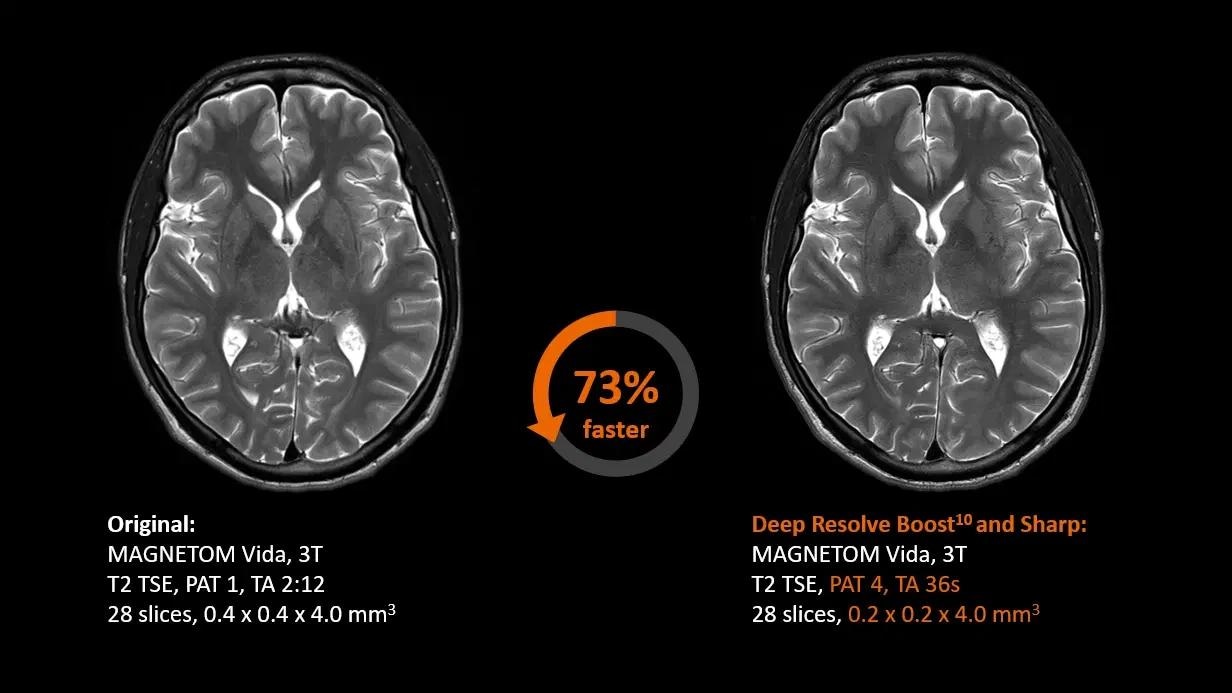

Deep Resolve5

Sharper images at a faster rate than ever before.

Deep Resolve—Faster than ever before

Deep Resolve is an AI-powered image reconstruction system that uses convolutional neural networks to expedite MR scans, making them faster than ever before. Faster scans increase workflow efficiency while boosting patient satisfaction.

Deep Resolve’s raw data-to-image reconstruction and extremely quick acquisition are game changers in MRI, allowing for the generation of actionable insights that can be diagnostically useful. In a secure digital environment, an open interface is intended to foster cooperation and co-creation. Deep Resolve technology is one step closer to creating a healthy world for all.